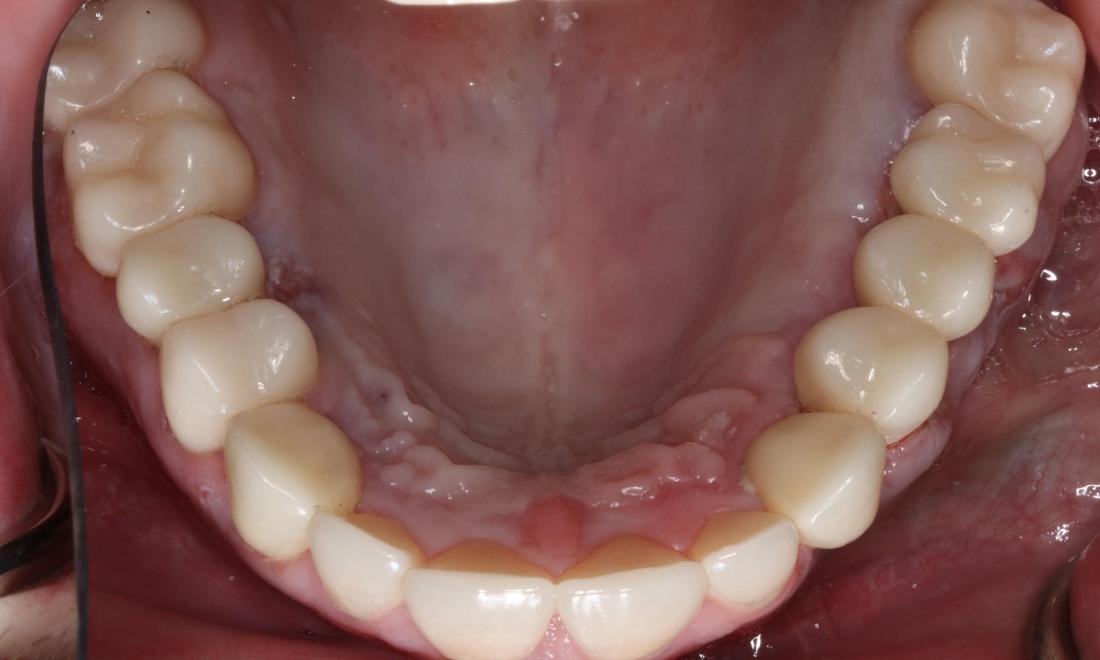

After a long journey to sobriety, this patient was ready to get his mouth healthy along with the rest of his body.  He was ready to smile with his kids again and jumpstart his new career.

Overhead view of mouth before complete smile makeover, nashville tn Overhead view of mouth after complete smile makeover, nashville tn